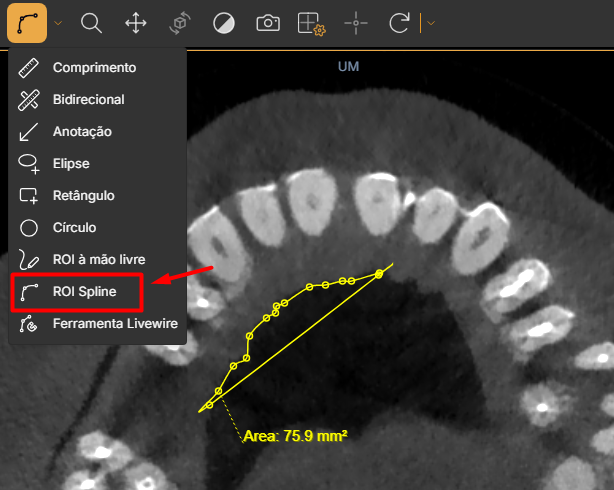

8. ROI Spline

Desenha uma região suave baseada em curvas spline (curva suave) oferecendo maior precisão especialmente em cotornos não lineares.

Uso prático: clique sobre a imagem com o botão esquerdo do mouse nos locais que deseja contornar, cada clique cria um ponto de controle da curva, eles irão se conectar criando linhas suaves, após completar a região dê dois cliques no ponto final.